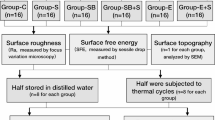

Human maxillary central incisors were endodontically treated, decoronated, and divided into 4 groups (n = 48). The following specimen preparation was performed: (I) adhesive core-and-post build-up (control), (II) as (I) and 2 mm apical root resection (AR), (III) before adhesive core-and-post build-up teeth were shortened 2 mm coronally (OE) (IV) as (I), but specimens were embedded 4 mm instead of 2 mm below the CEJ (SCL), group (V) implant-borne restoration with individual all-ceramic abutments (n = 12; ∅4.1/l = 12 mm) (IBR). All specimens received all-ceramic crowns, thermo-mechanical (TML), and subsequent linear loading (LL) until failure. RCRR were calculated and log-rank, Kruskal–Wallis, Mann–Whitney U, ANOVA, and chi-square tests applied (p = 0.05).

Human maxillary incisors were selected from a tooth bank and stored at room temperature in a 0.5% chloramine solution. To ensure the use of teeth of comparable dimension within the groups, mesio-distal (MD) and facial–lingual (FL) dimensions were measured at the level of the cemento-enamel junction (CEJ). Tooth size was calculated as the product of MD × FL. Teeth with extremely short (< 12.3 mm) or long root length (> 16.7 mm) were excluded. Specimens were randomly distributed into 4 groups (n = 12) by means of a ten-digit random table to either no change to crown-to-root ratio (control, group I), apical root resection (group II), extrusion (group III), and surgical crown lengthening (group IV). The crowns of teeth in groups I and II were cut 2 mm coronally to the CEJ and in groups III and IV at CEJ level. Root canals were enlarged using the X-Smart (Dentsply DeTrey, Konstanz, Germany) and NiTi-files to size F2 (Protaper, Dentsply DeTrey) and rinsed with 3% sodium hypochlorite. Root canals were filled by corresponding size F2 of gutta-percha (Protaper, Dentsply DeTrey) and sealer (AH 26 Plus Jet, Dentsply DeTrey).

The roots of the specimens of groups I and II were blocked out with wax 2 mm and specimens of group III and IV 4 mm below the CEJ. To imitate a periodontium and physiological tooth mobility, roots of the teeth were covered with a layer of silicone (Mollosil Plus, Detax, Ettlingen, Germany) as described elsewhere [13]. All teeth and implants (group V, n = 12) were embedded in acrylic resin (Technovit 4004, Kulzer, Wehrheim, Germany). To prevent overheating, the teeth were immersed in water for 5 min during resin polymerization.

Tooth-based restoration, groups I–IV

Post-space preparation was performed 8 mm within the root canal in one sequence as described by the manufacturer. All restorative steps were performed using the Dentsply Core & Post System (CTS, Dentsply DeTrey).

The etch-and-rinse and bonding procedure was performed according to the manufacturer’s instruction. The root canal and the coronal tooth surface were etched with 36% phosphoric acid (Conditioner 36, Dentsply DeTrey) for 15 s. After water rinsing and air-drying, the adhesive was applied and left for 20 s (XP Bond, Self-cure Activator, Dentsply DeTrey, 1:1 ratio, mixed for 2 s). A glass fibre post (size 2 (red), Ø 1.25 mm, X-Post, CTS, Dentsply DeTrey) was treated with adhesive and was luted with core build-up material in a staged procedure using a dual curing core-and-post composite (Core-X™ flow, Dentsply DeTrey). The core was built up by means of a strip crown (upper central incisor, Frasaco, Tettnang, Germany) and polymerized from the incisal, palatal, and facial aspect for 20 s each. All teeth were prepared with a circumferential 0.8 mm shoulder and 6° convergence angle to meet all-ceramic crown requirements. To achieve an equal crown length, the core build-ups were similar in length for group I to III (4 mm) and for group IV (6 mm). The margin was located 2 mm below the core build-up in dentin to ensure proper ferrule design. Specimens were scanned with an intraoral scanner (Trios, 3Shape, Kopenhagen, Dänemark); models were milled out of polyurethan. Crowns were constructed digitally (Dental Designer, 3Shape, Copenhagen, Denmark), subsequently milled in wax (Organical Multi, R + K CAD/CAM, Berlin, Germany), transferred to lithium disilicate (IPS e.max, Ivoclar Vivadent, Schaan, Germany), and glazed (IPS e.max Ceram Glaze, Ivoclar Vivadent). Crown width was 2 mm incisally, 1.5 mm in the middle, and 0.8 mm at the preparation margin. Crown height was 8 mm, except in group IV (10 mm) (Figs. 1 and 2).

Implant-based restoration, group V

Dental implants (length 12 mm, diameter 4.1 mm, Straumann Bone Level, Freiburg, Germany) were restored with titanium alloy base (RC Variobase Abutment, diameter 4.5 mm, length 3.5 mm, Straumann, Germany) with lithium disilicate abutments (IPS e.max, Ivoclar Vivadent, Schaan, Liechtenstein). Twelve identical lithium disilicate abutments were modelled in wax (Dental Designer, 3Shape, Copenhagen), milled (Organical Multi, R + K CAD/CAM, Berlin), and transferred in lithium disilicate (IPS e.max, Ivoclar Vivadent). Abutment measures were equivalent to cores of group I. Abutments were luted on the alloy bases with self-adhesive luting composites (IPS E.max Abutment Solution Cem Kit, Ivoclar Vivadent). Abutments were screwed in with 35Ncm. Crowns were etched 20 s with fluoric acid (Vita Ceramics Etch, Vita, Bad Säckingen, Germany), cleaned with water and isopropanol, silanized (Monobond Plus, Ivoclar Vivadent, Schaan) for 60 s, and self-adhesively luted (SmartCem Dentsply DeTrey). Final light curing was performed for 20 s from each restoration side.

Loading protocol

Thermal and mechanical loading (TML) was performed (parameters: 6000 thermal cycles, 5 °C/ 55 °C, 2 min each cycle; dist. water; 1.2 × 106 mastication cycles with 50N) to simulate 5 years of clinical service [14]. The restorations were loaded under 135°, 3 mm below the incisal edge, on the palatal surface of the crown. After TCML, tooth mobility was measured three times for each specimen by means of a Periotest device perpendicular to tooth and implant axis (Periotest Classic, Medizintechnik Gulden, Germany). Specimens were statically loaded in a universal testing machine (Zwick 1446, Zwick, Ulm, Germany; v = 1 mm/min) until failure. Failure detection was set at a 10% loss of the maximum applied force. A 0.3-mm-thick tin foil was positioned between the steel piston and the palatal crown surface to reduce excessive stress concentrations (Fig. 3).

Calculation of crown-to-root ratio (RCRR)

The length of the prosthetic crown LC was defined with 8 mm for groups I to III and 10 mm for group IV. The distance crown margin to crestal alveolar bone was 2 mm in order to simulate biologic width (LBW). The sum of LC + LBW was defined as effective crown height CE. The root length LR is the distance from the apex to the CEJ. The effective root length RE is defined as length of the root LR within alveolar bone [15]. In groups II, III, and IV, RE was 2 mm smaller than LR due to simulated apical root resection, extrusion, or crown lengthening, respectively (RE = LR − 2 mm). In groups II and III, the effective crown height CE was equivalent to that of group I. For group IV, CE of group IV was calculated from LC + LBW + 2 mm of crestal bone resection.